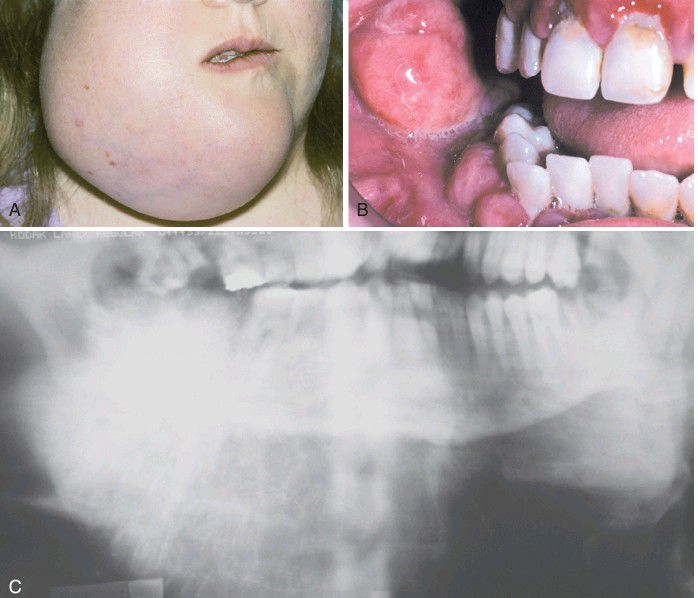

Osteosarcoma

. A, This massive tumor had been present for many months before the patient sought treatment. B, Intraoral photograph of the tumor mass. C, The panoramic radiograph shows a “sunburst” pattern of trabeculation.